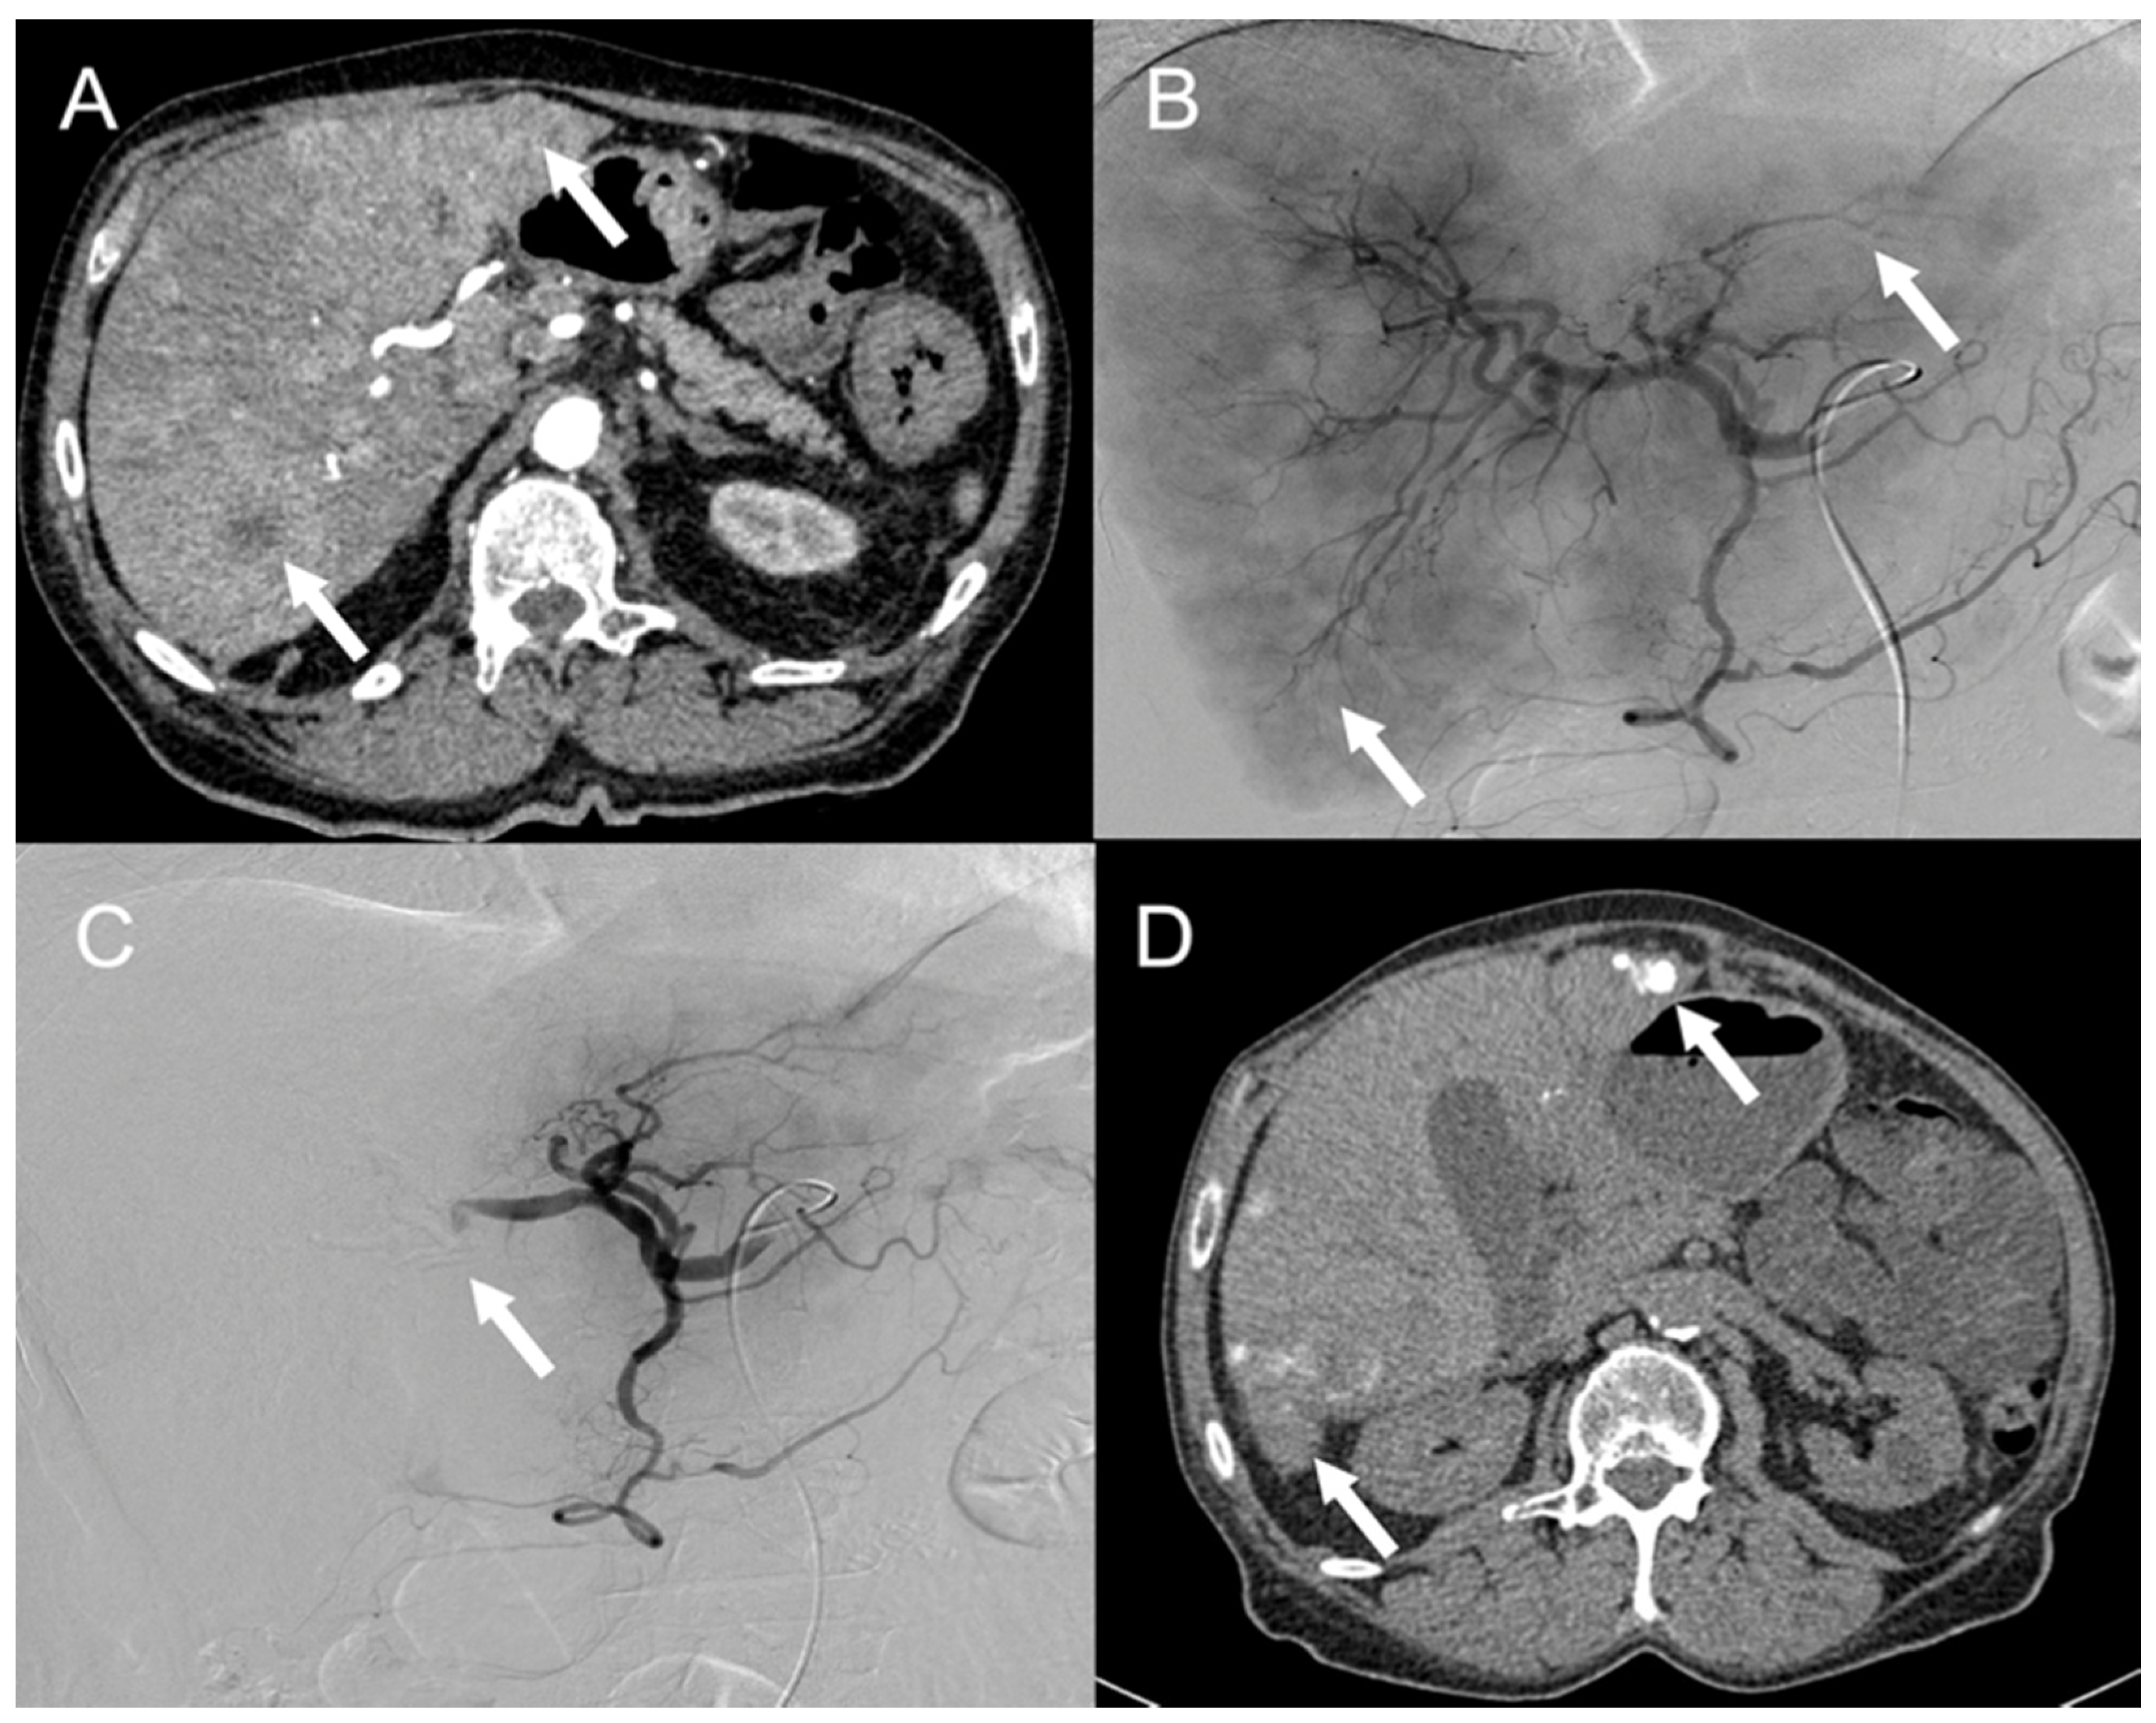

- Kennedy, A.; Bester, L.; Salem, R.; Sharma, R.A.; Parks, R.W.; Ruszniewski, P. Role of hepatic intra-arterial therapies in metastatic neuroendocrine tumours (NET): Guidelines from the NET-Liver-Metastases Consensus Conference. HPB 2015, 17, 29–37. [Google Scholar] [CrossRef] [PubMed] [Green Version]

- Lee, E.; Pachter, H.L.; Sarpel, U. Hepatic Arterial Embolization for the Treatment of Metastatic Neuroendocrine Tumors. Int. J. Hepatol. 2012, 2012, 471203. [Google Scholar] [CrossRef] [PubMed] [Green Version]

- Barat, M.; Cottereau, A.-S.; Kedra, A.; Dermine, S.; Palmieri, L.-J.; Coriat, R.; Dautry, R.; Tselikas, L.; Soyer, P.; Dohan, A. The Role of Interventional Radiology for the Treatment of Hepatic Metastases from Neuroendocrine Tumor: An Updated Review. J. Clin. Med. 2020, 9, 2302. [Google Scholar] [CrossRef] [PubMed]

- Tai, E.; Kennedy, S.; Farrell, A.; Jaberi, A.; Kachura, J.; Beecroft, R. Comparison of Transarterial Bland and Chemoembolization for Neuroendocrine Tumours: A Systematic Review and Meta-Analysis. Curr. Oncol. 2020, 27, 537–546. [Google Scholar] [CrossRef]

- Minh, D.D.; Chapiro, J.; Gorodetski, B.; Huang, Q.; Julius, C.; Smolka, S.; Savic, L.J.; Wainstejn, D.; Lin, M.; Schlachter, T.; et al. Intra-arterial therapy of neuroendocrine tumour liver metastases: Comparing conventional TACE, drug-eluting beads TACE and yttrium-90 radioembolisation as treatment options using a propensity score analysis model. Eur. Radiol. 2017, 27, 4995–5005. [Google Scholar] [CrossRef] [PubMed]